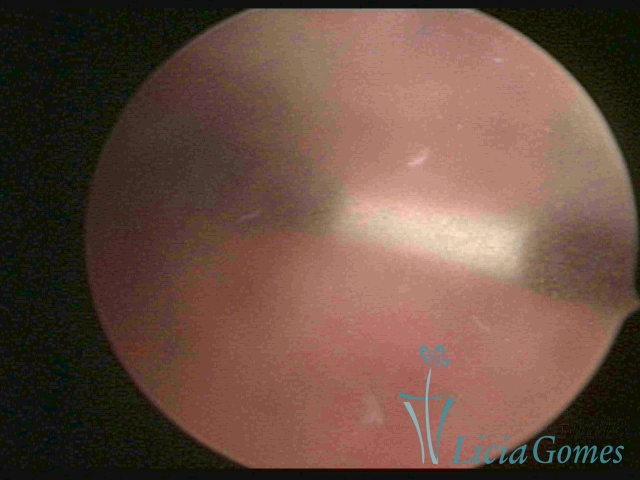

Myometrium punctured IUD

×